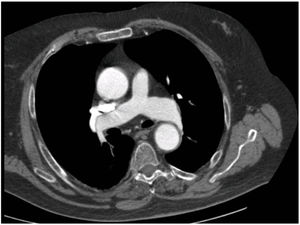

We report the case of a 76-year-old man with a history of obesity, prostate cancer, and vertebrobasilar and cerebellar stroke 5 years previously with no sequelae, unconfirmed suspected sleep apnea-hypopnea syndrome (SAHS) and ostium secundum-type interatrial communication. He presented with dyspnea and hypoxemia that had commenced a few months before admission, for which he was prescribed home oxygen, although the cause of the hypoxemia was never determined. At the time of admission, he had dyspnea at rest and presented disorientation and agitation, central cyanosis, tachypnea, inspiratory crackles in the right base and posterior plane, normal heart sounds with no signs of right overload and severe hypoxemia without hypercapnia. Chest radiograph showed no infiltrates, and pulmonary embolism was ruled out by computed tomography (CT) angiography, observing only some laminar atelectasia in dependent segments. Nevertheless, it was noted that the contrast density was higher in the aorta than in the pulmonary artery, despite the presence of residual contrast in the vena cava; it was also observed that the ascending aorta was dilated (Fig. 1). Arterial blood gas analysis with oxygen delivered by nasal cannula at a flow rate of 4Lpm in decubitus showed pH: 7.42; PaCO2: 38mmHg; PaO2: 56mmHg; HCO3: 25mEquiv./L; and SaO2: 89%. Transthoracic echocardiography (TTE) found good biventricular function with abnormal left ventricular relaxation, with no indirect signs of interatrial communication or pulmonary hypertension.